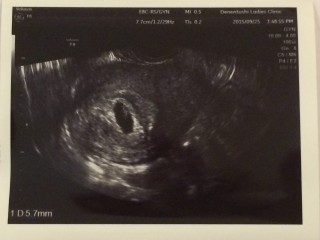

前回3.9㎜だった胎嚢も1週間で18㎜まで成長して、赤ちゃんの姿とピコピコ凄い早さで動いてる心拍確認できました!